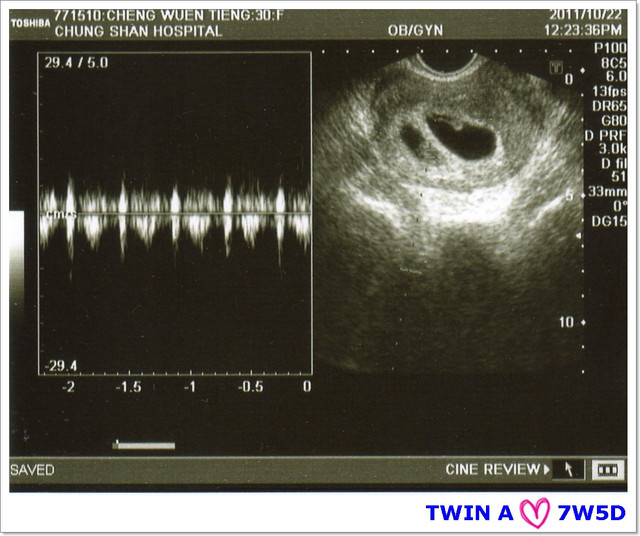

接著~要聽寶寶的心跳,羅醫生請我憋氣5秒,超音波室出現咚咚~咚咚~咚咚的心跳聲,

隔了一個禮拜,寶寶們都有乖乖的在媽咪的肚子裡長大喲:)